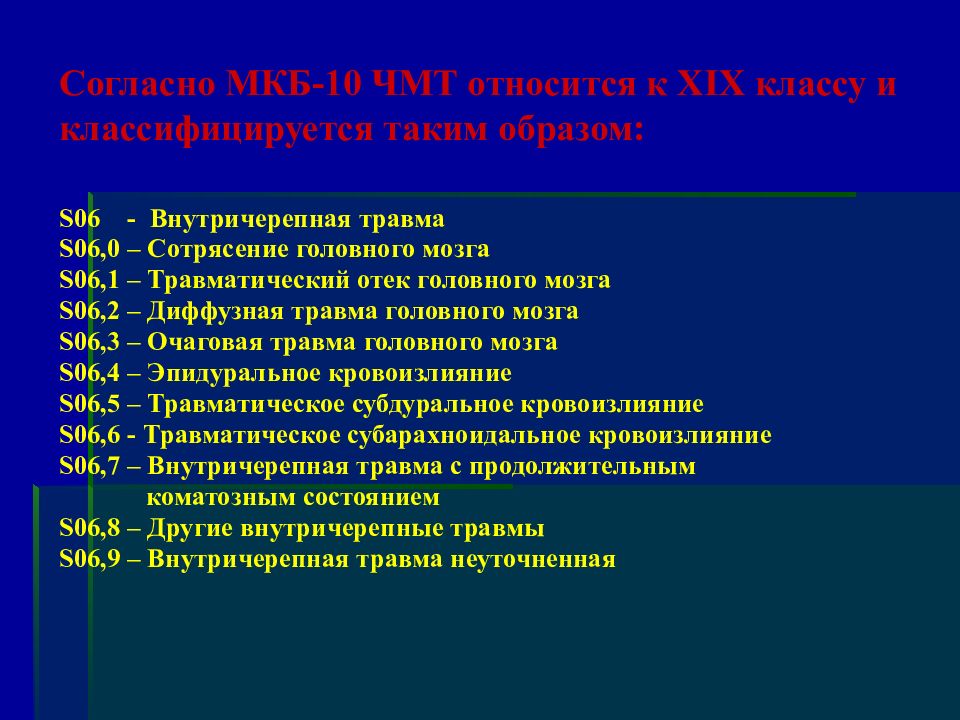

Код мкб 10 атерома головы

Код мкб 10 атерома головы 109 фото